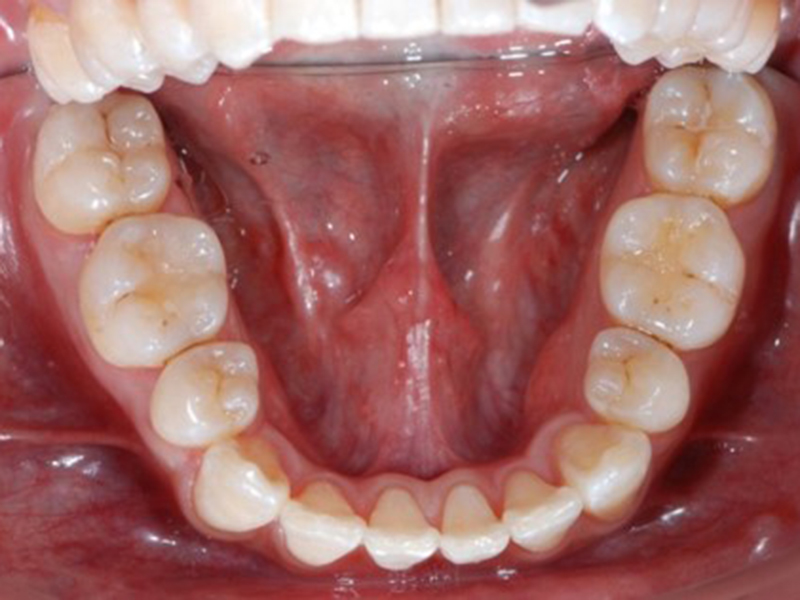

▼ ケース5 下顎前歯部叢生症例

初診時口腔内写真